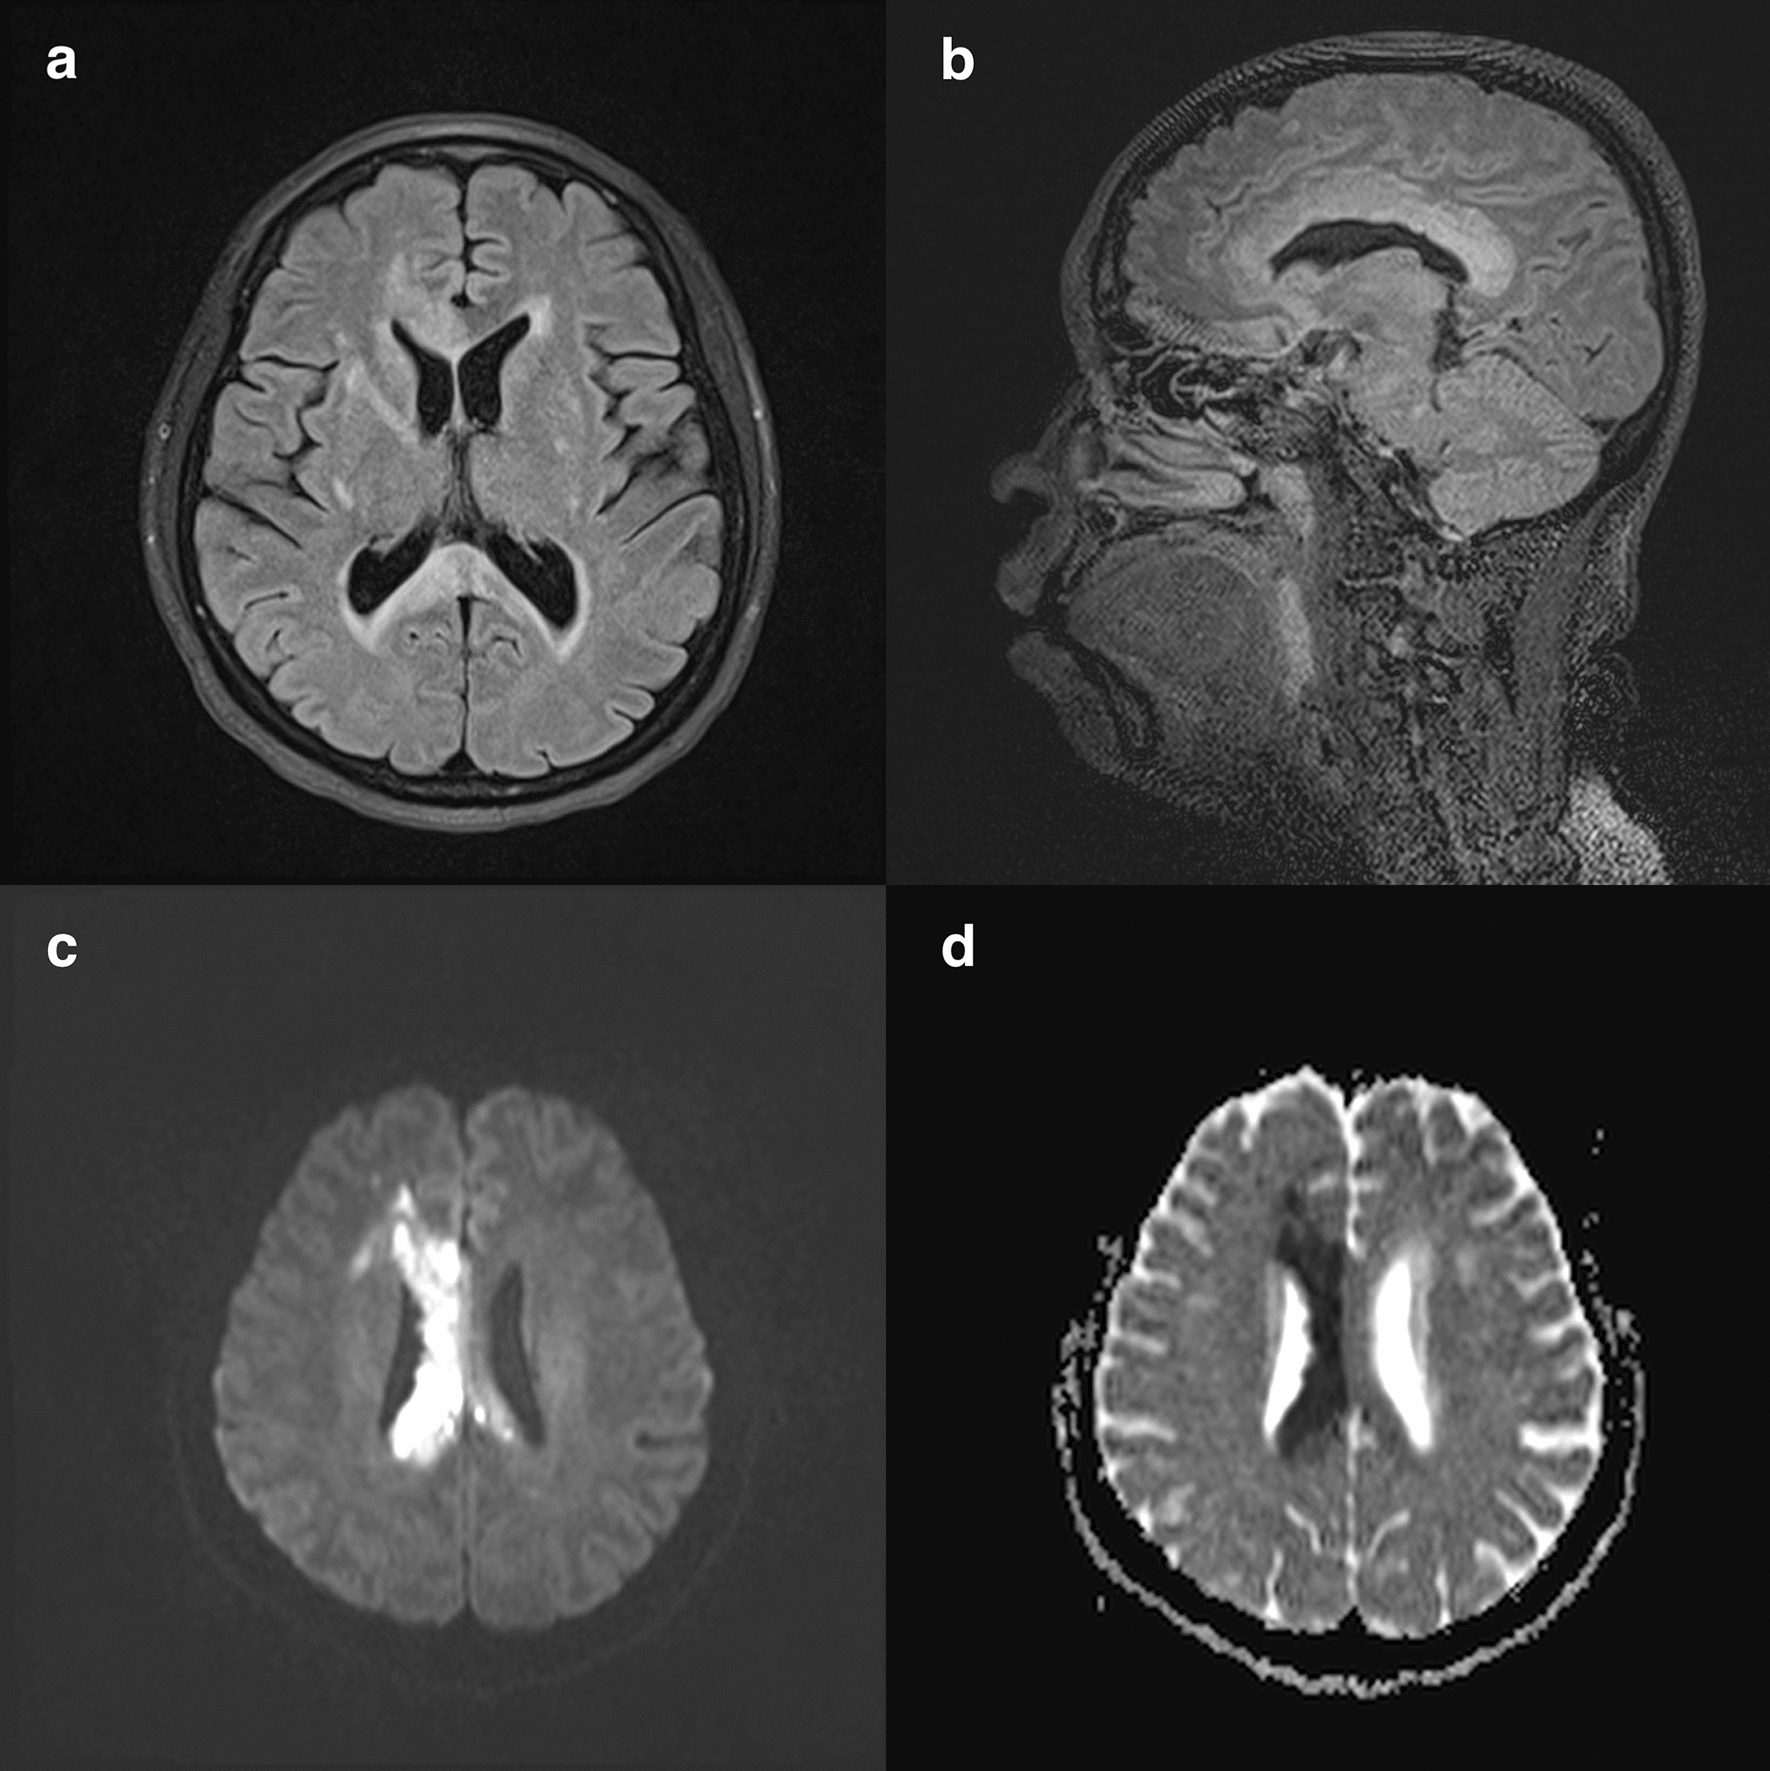

A 40-year-old woman with no previous medical illness presented with sudden onset of left sided body weakness and facial asymmetry for two days. On examination, she had left lower facial palsy and left hemiparesis with muscle power of MRC grade 2/5. The higher cortical function and sensory modalities were normal. There were no visual disturbance or features of connective tissue disease. Non-contrasted CT brain showed hypodensity in the right corpus callosum. Magnetic resonance imaging (MRI) of the brain revealed hyperintense T2/FLAIR signals in corpus callosum with restricted diffusion (Fig. 1). There were also evidence of lacunar infarcts in the right corona radiata and putamen. MR angiogram of the brain showed atherosclerotic disease with focal stenosis of the right A1 segment. Electrocardiogram, echocardiogram and 24 h Holter monitoring were unremarkable. She was found to have diabetes mellitus with fasting serum glucose of 16.2 mmol/L and HbA1c of 11.7%. Peripheral blood count, renal and liver function, erythrocyte sedimentation rate were normal. Anti-nuclear antibody, anti-phospholipid antibodies, serum aquaporin-4 and myelin oligodendrocyte glycoprotein antibodies were not detected. The diagnosis of corpus callosum infarction was made and she was treated with oral aspirin, atorvastatin and subcutaneous insulin. Despite inpatient rehabilitation, she remained disabled with modified Rankin scale of 4/6 after one month.

Fig. 1

MRI of the brain showed hyperintense signals in the corpus callosum, especially the splenium and appearing as an “arch-bridge” pattern on T2/FLAIR sequences. a, b There were also hyperintense lesions in the corona radiata and putamen suggestive of old lacunar infarctions. On the DWI/ADC sequences, the entire corpus callosum showed significant restricted diffusion particularly on the right side (c, d)